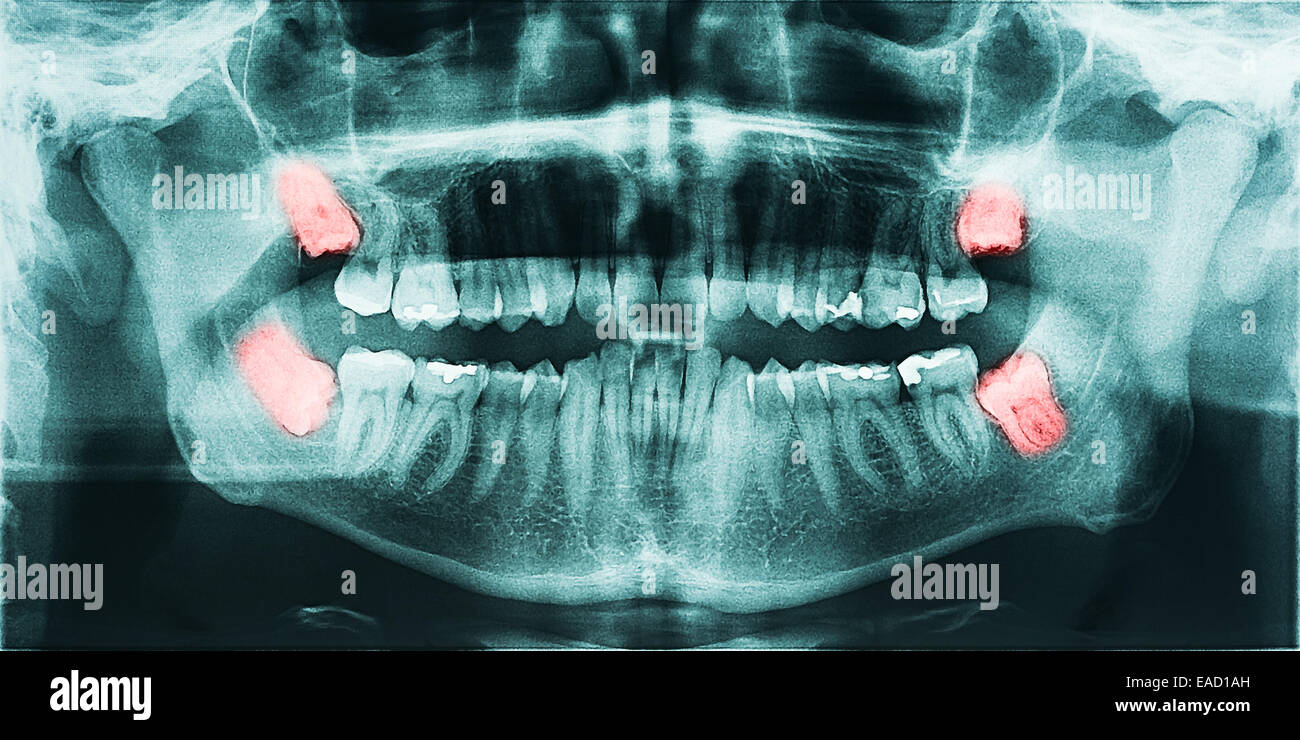

Panoramic X-ray Image Of Teeth And Mouth With Wisdom Teeth | Parkview

fountainhillsdentist.comwisdom teeth ray mouth panoramic back tooth

fountainhillsdentist.comwisdom teeth ray mouth panoramic back tooth